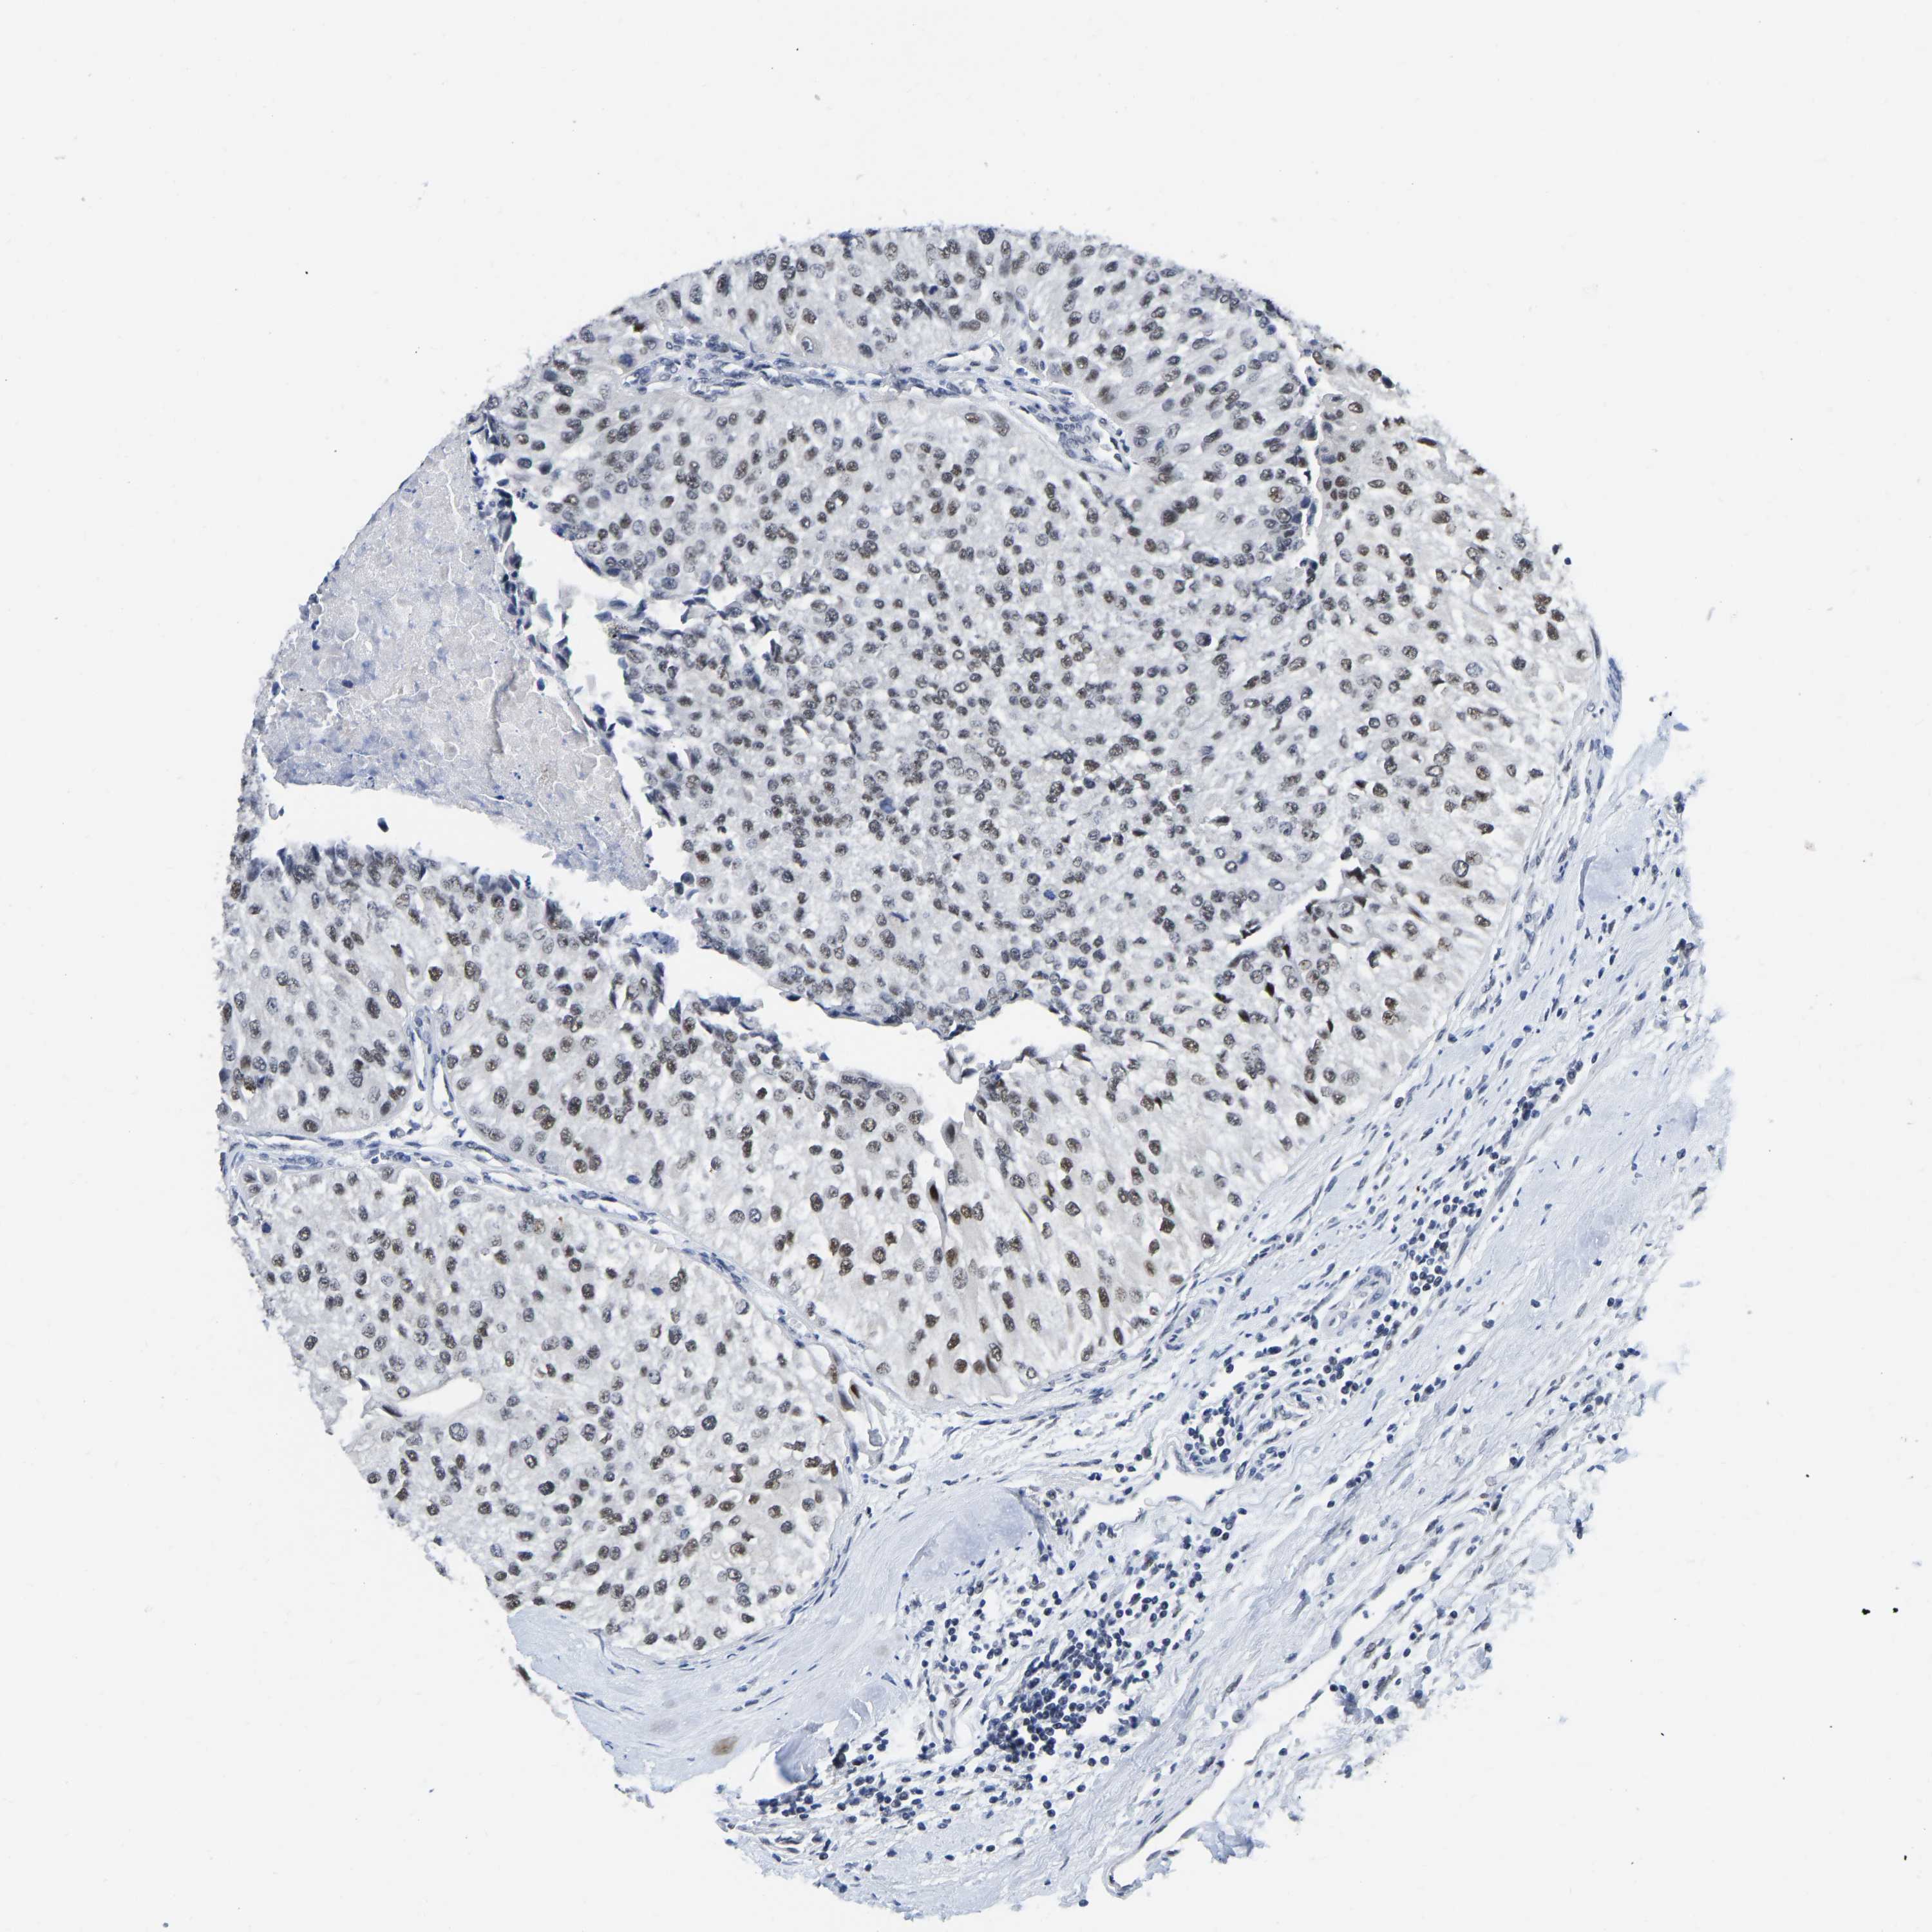

UROTHELIAL CANCER - Protein expressioni

A mouse-over function shows sample information and annotation data. Click on an image to view it in a full screen mode. Samples can be filtered based on level of antibody staining by selecting one or several of the following categories: high, medium, low and not detected. The assay and annotation is described here.

Antibody stainingi

Antibody staining in the annotated cell types in the current human tissue is reported as not detected, low, medium, or high, based on conventional immunohistochemistry profiling in selected tissues. This score is based on the combination of the staining intensity and fraction of stained cells.

Each image is clickable and will lead to virtual microscopy that enables deeper exploration of all samples and also displays staining intensity scores, fraction scores and subcellular localization as well as patient and tissue information for each sample.

Antibody CAB019416

Staining

High

Medium

Low

Not detected

Intensity

Strong

Moderate

Weak

Negative

Quantity

>75%

75%-25%

<25%

None

Location

Nuclear

Cytoplasmic/membranous

Cytoplasmic/membranous,nuclear

Urothelial carcinoma, Low grade

Urothelial carcinoma, High grade